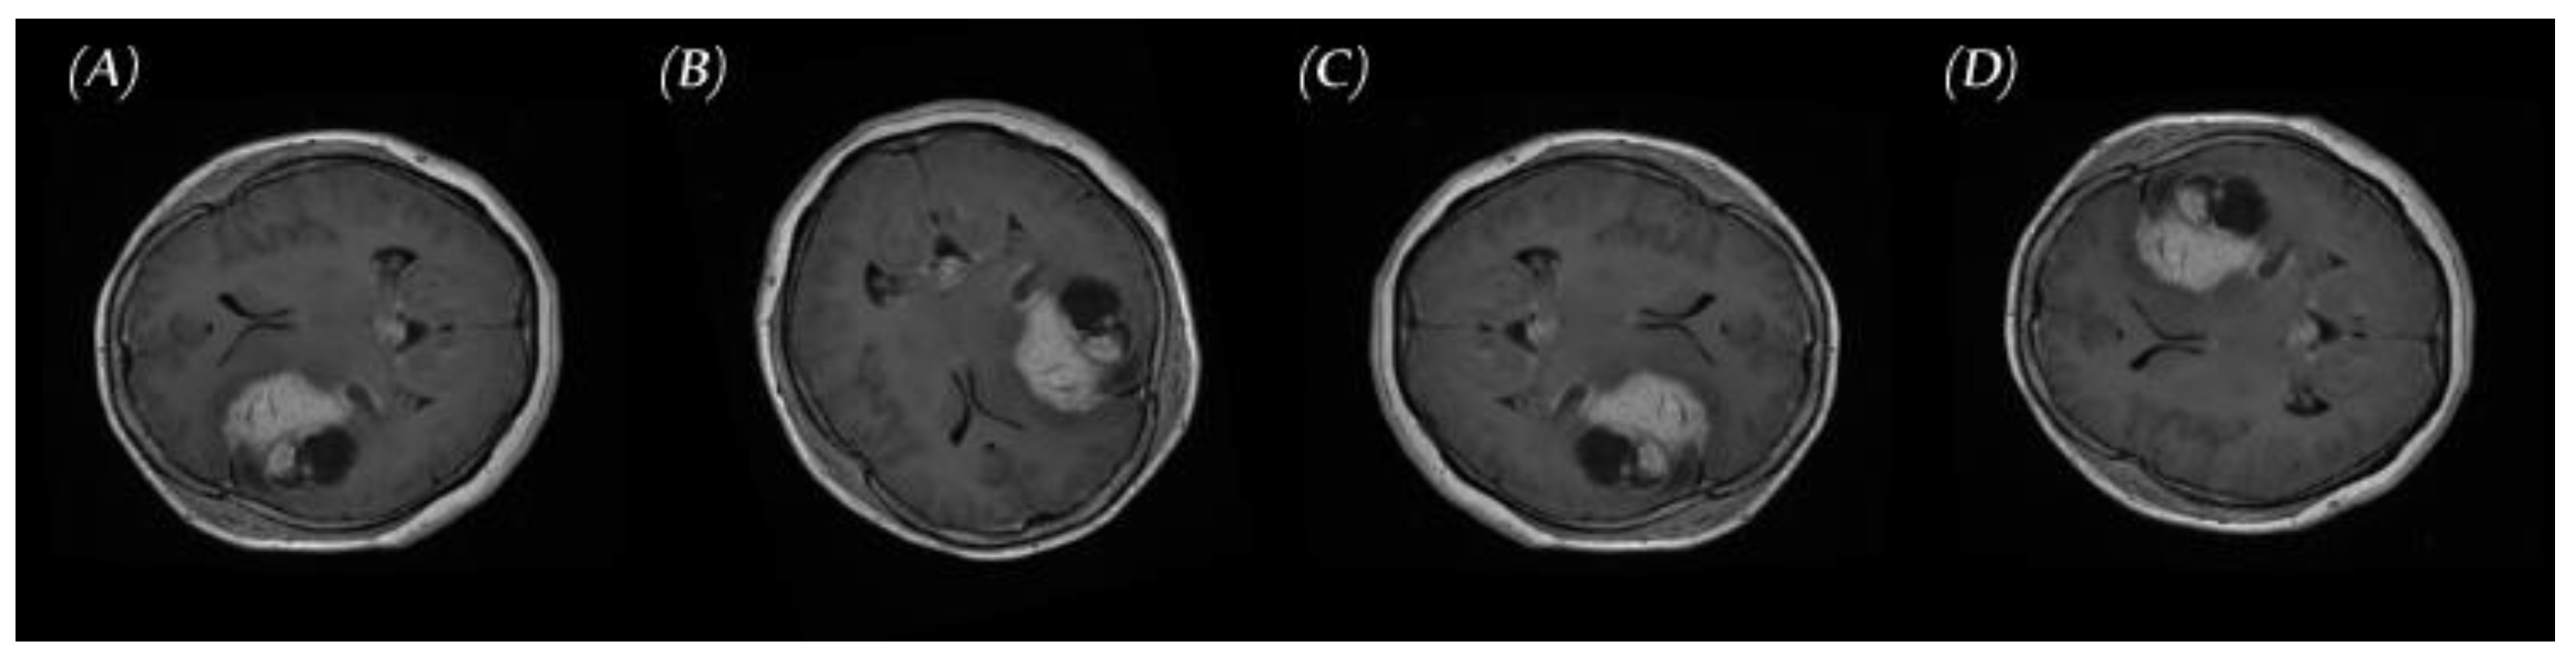

2.2.2. PGGAN-Based Data Augmentation